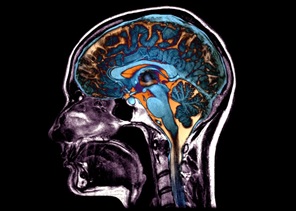

Một số phần của não bộ có xu hướng teo lại và biến dạng (ảnh: Zephyr/SPL).

TS Andrei Irimia, Đại học Southern California (Hoa Kỳ), người không tham gia vào nghiên cứu này đánh giá, kết quả của công trình này rất đáng chú ý, giúp nâng cao đáng kể sự hiểu biết của các nhà khoa học về lão hóa. Trước nghiên cứu này, chúng ta biết rằng, cấu trúc não thay đổi theo tuổi tác và bệnh tật, tuy nhiên, khả năng nắm bắt sự tương tác phức tạp giữa chúng vẫn còn rất khiêm tốn. Theo TS Christos Davatzikos, chuyên gia hình ảnh y sinh tại Đại học Pennsylvania (Hoa Kỳ), lão hóa không chỉ gây ra tóc bạc mà còn dẫn đến những thay đổi trong cấu trúc não bộ có thể nhìn thấy qua các hình ảnh chụp cộng hưởng từ (MRI). Nhưng những biến đổi này là rất nhỏ, vì vậy mắt người không thể nhận ra các mô hình thay đổi trong não có liên quan đến sự suy giảm này. Các nghiên cứu trước đây đã chứng minh rằng, phương pháp học máy có thể “tìm ra” những dấu vết tinh vi của lão hóa từ dữ liệu MRI. Tuy nhiên, những nghiên cứu đó thường bị hạn chế về phạm vi và hầu hết chỉ bao gồm dữ liệu từ một số lượng người tương đối nhỏ. Để xác định các mô hình rộng hơn, nhóm của TS Christos Davatzikos đã mất 8 năm để hoàn thành và công bố kết quả của nghiên cứu này. Nhóm nghiên cứu sử dụng một phương pháp học sâu gọi là Surreal-GAN (phương pháp học biểu diễn bán giám sát được thiết kế để xác định tính không đồng nhất liên quan đến bệnh tật giữa các nhóm bệnh nhân). TS Christos Davatzikos và cộng sự đã đào tạo thuật toán trên các hình ảnh MRI của não từ 1.150 người khỏe mạnh ở độ tuổi 20-49 và 8.992 người lớn tuổi, bao gồm những người đã trải qua suy giảm nhận thức. Điều này đã dạy thuật toán nhận ra các đặc điểm lặp lại của bộ não lão hóa, từ đó cho phép tạo ra một mô hình nội bộ về các cấu trúc giải phẫu có xu hướng thay đổi cùng lúc so với các cấu trúc có xu hướng thay đổi độc lập. Các nhà nghiên cứu sau đó đã áp dụng mô hình này vào hình ảnh MRI của gần 50.000 người tham gia các nghiên cứu về lão hóa và sức khỏe thần kinh. Qua phân tích, họ đã phát hiện ra 5 mô hình teo não khác nhau. Chứng sa sút trí tuệ (giai đoạn sớm là chứng suy giảm nhận thức nhẹ) có liên quan đến 3/5 mô hình nghiên cứu. Đặc biệt, các mô hình này có thể dự đoán khả năng teo não trong tương lai. Theo TS Christos Davatzikos, nếu muốn dự đoán sự chuyển biến từ nhận thức bình thường sang suy giảm nhận thức nhẹ, một mô hình có thể giúp dự đoán chính xác những biến đổi này. Khi bệnh tiến triển đến giai đoạn muộn hơn, việc sử dụng thêm một mô hình thứ hai sẽ nâng cao độ chính xác của dự đoán. Kết quả kết hợp 3 mô hình đã cho thấy những dự đoán rất chính xác nguy cơ tử vong. Bên cạnh đó, nhóm nghiên cứu còn phát hiện ra mối liên hệ rõ ràng giữa một số mô hình teo não và các yếu tố sinh lý, môi trường, bao gồm việc uống rượu và hút thuốc, cũng như các dấu hiệu di truyền và sinh hóa liên quan đến sức khỏe. TS Christos Davatzikos cho rằng, những kết quả này có thể phản ánh ảnh hưởng của sức khỏe tổng thể đối với sức khỏe thần kinh, vì tổn thương các hệ cơ quan khác có thể ảnh hưởng đến não bộ. Các nhà khoa học cho biết, họ đang tìm cách làm việc với các tập dữ liệu bao gồm nhiều tình trạng thần kinh hơn với sự đa dạng về chủng tộc và sắc tộc.BL (theo Nature)